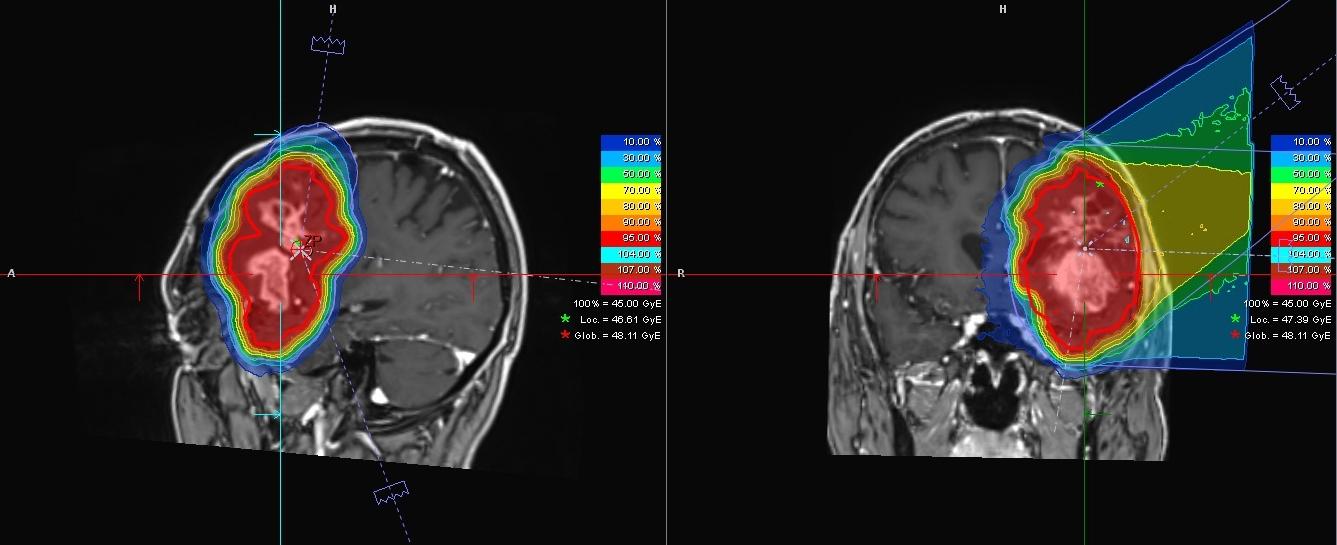

Zwei MRT-Aufnahmen eines Patienten mit Glioblastom

Die Aufnahmen zeigen das Glioblastom eines 55-jährigen Patienten in der Nähe der linken Schläfe. Der Tumor wurde mittels Magnetresonanztomographie (MRT) aus verschiedenen Perspektiven aufgenommen. Die Farben zeigen die Verteilung der geplanten Strahlendosis: Im Bereich des Tumors ist sie am höchsten (rot), mit zunehmender Entfernung zum Tumor wird sie immer niedriger. © Universitätsklinikum Heidelberg